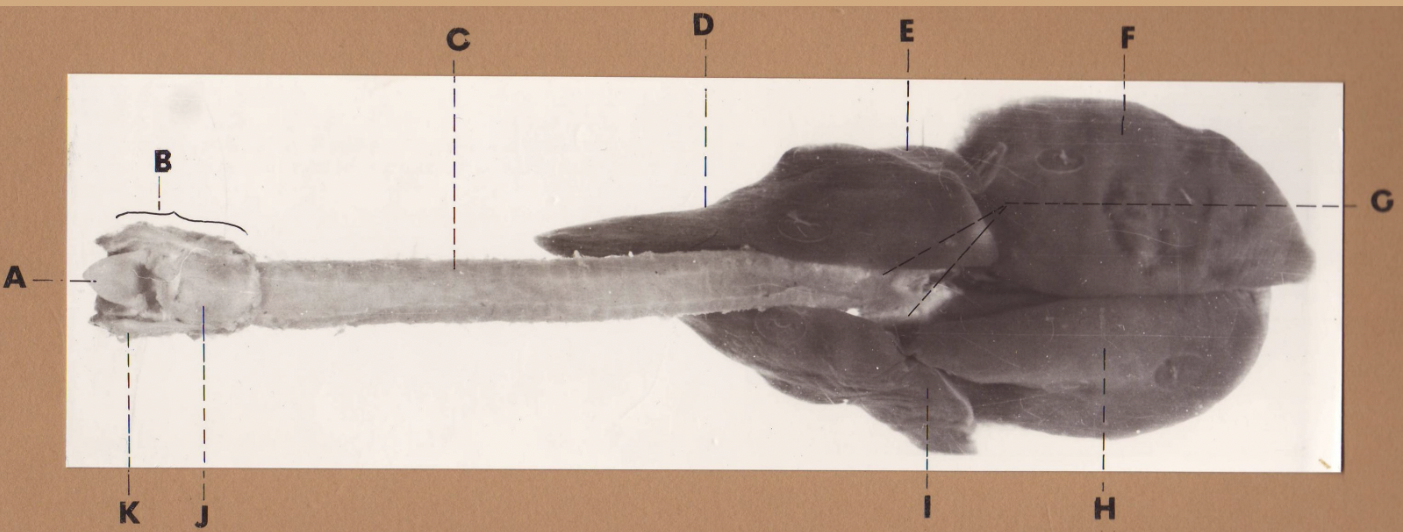

A

(cat larynx/trachea/lungs, dorsal)

epiglottis

B

(cat larynx/trachea/lungs, dorsal)

larynx

C

(cat larynx/trachea/lungs, dorsal)

trachea

D

(cat larynx/trachea/lungs, dorsal)

R cranial lobe

E

(cat larynx/trachea/lungs, dorsal)

middle lobe

F

(cat larynx/trachea/lungs, dorsal)

R caudal lobe

G

(cat larynx/trachea/lungs, dorsal)

primary bronchi

H

(cat larynx/trachea/lungs, dorsal)

L caudal lobe

I

(cat larynx/trachea/lungs, dorsal)

L cranial lobe

J

(cat larynx/trachea/lungs, dorsal)

cricoarytenoideus dorsalis m

K

(cat larynx/trachea/lungs, dorsal)

thyroid

A

(cat larynx/trachea/lungs, dorsal)

epiglottis

B

(cat larynx/trachea/lungs, dorsal)

larynx

C

(cat larynx/trachea/lungs, dorsal)

trachea

D

(cat larynx/trachea/lungs, dorsal)

R cranial lobe

E

(cat larynx/trachea/lungs, dorsal)

middle lobe

F

(cat larynx/trachea/lungs, dorsal)

R caudal lobe

G

(cat larynx/trachea/lungs, dorsal)

primary bronchi

H

(cat larynx/trachea/lungs, dorsal)

L caudal lobe

I

(cat larynx/trachea/lungs, dorsal)

L cranial lobe

J

(cat larynx/trachea/lungs, dorsal)

cricoarytenoideus dorsalis m

K

(cat larynx/trachea/lungs, dorsal)

thyroid